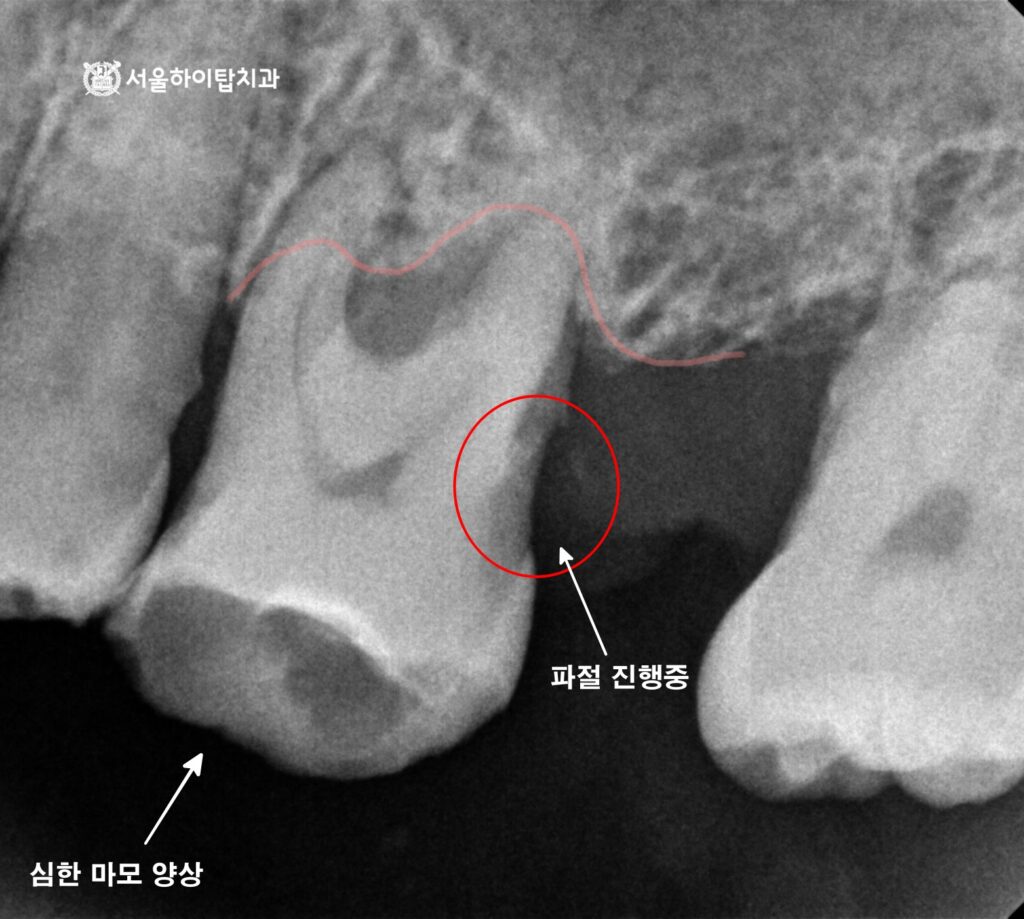

이제 간석역 치과 에서 문제가 되는 부위를 좀 더 자세히 살펴보겠습니다.

마찬가지로 임의로 표시해 둔 선을 기준으로 보면,

치조골이 대부분 소실되어 잇몸이 치아를 겨우 지탱하고 있는 상태임을 확인할 수 있습니다.

또한 방사선 사진에서도 확인될 정도로

교합면 마모가 심하게 진행되어 있으며,

치아의 mesial(근심면) 부위에는 파절 소견이 관찰됩니다.

이처럼 골 소실이 진행된 상태에서 마모와 파절까지 동반된 경우에는,

자연치를 보존하더라도 장기적인 안정성을 기대하기 매우 어렵습니다.

특히 잇몸뼈의 지지가 충분하지 않은 상태에서는

보존이나 보철 치료를 시행하더라도 재파절이나 염증 재발의 가능성이 높아,

발치를 통한 감염원 제거가 불가피한 상황으로 판단되는 경우가 많습니다.

따라서 무리하게 유지하기보다, 임플란트를 통해

저작 기능과 구조적 안정성을 회복하는 것이

예후가 좋은 치료 방향으로 보여집니다.